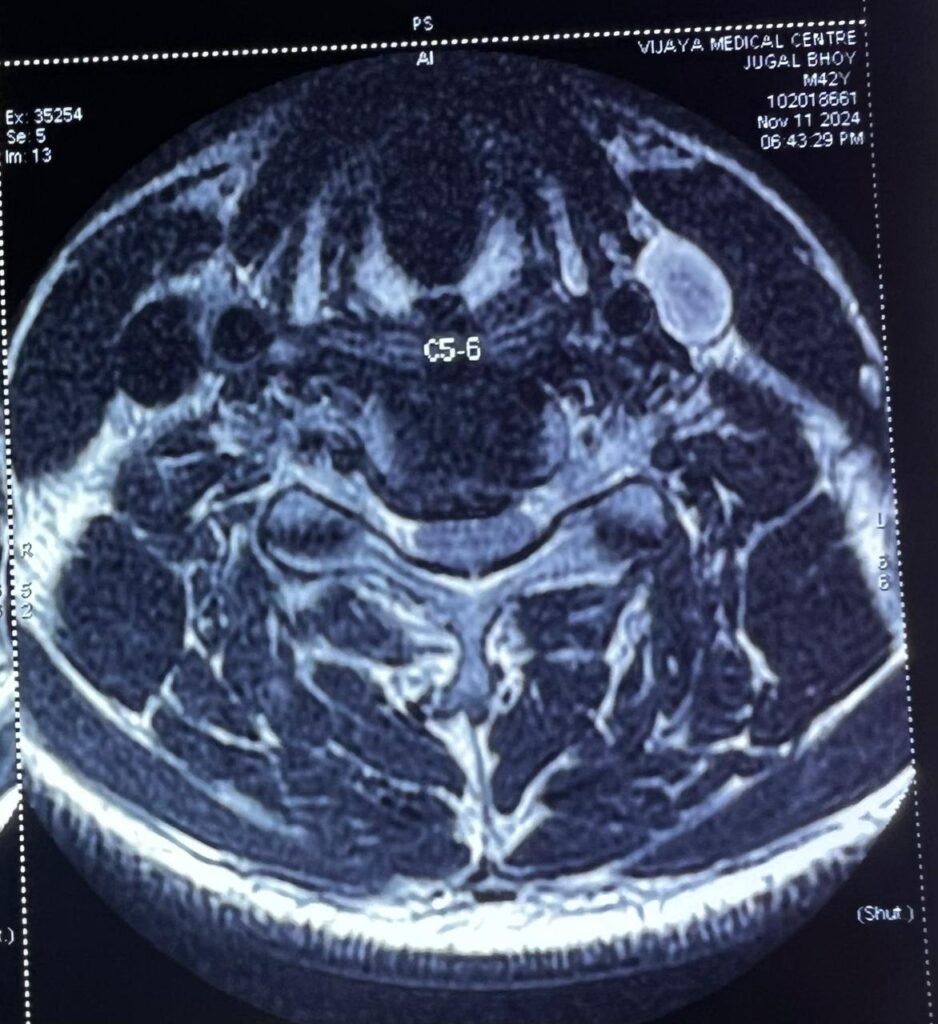

The scan showed disc prolapse at the C4-5 and C5-6 levels, with severe compression of the spinal cord. The paralysis of his right hand and leg was due to this compression. A diagnosis of cervical myelopathy was made , and as the patient was rapidly deteriorating, surgery was advised. The patient was taken up for surgery after a detailed discussion with his family regarding the risks, benefits, and possible outcomes. Surgery (Anterior Cervical Discectomy and Fusion (ACDF)) was done at the C4-5 and C5-6 levels.

The surgery involved approaching the spine from the front (anterior), removing the discs at C4-5 & C5-6 (discectomy), thereby relieving the pressure on the spinal cord, and placing a bone graft in the empty disc spaces (fusion) and fixing them with a titanium plate and screws.